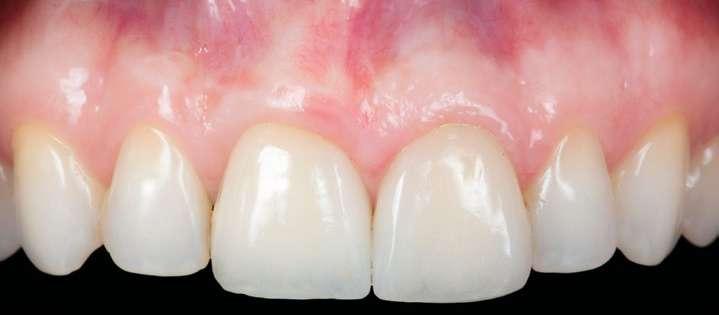

El diente 11 fue extraído (Figura 4), seguido por la preservación alveolar. Se realizó un injerto pediculado de espesor parcial rotado del paladar (Figura 5), junto con una membrana de colágeno reabsorbible, un xeno-injerto bovino y cianoacrilato sellando al alveolo (Figura 6). La provisionalización consistió en un puente adhesivo de resina con dos alas de metal. El alveolo se dejó cicatrizar durante 6 meses, después de los cuales se tomó una impresión digital así como un escáner CBCT (Figura 7). Se llevó

a cabo una planificación digital para una cirugía guiada de implante en una posición protéticamente ideal (Figura 8). El implante 11 se colocó completamente guiado a través de una férula (Figura 9). Las dimensiones del reborde alveolar eran ideales para la colocación del implante en una posición atornillada (Figura 10), al igual que la calidad del hueso cicatrizado. Un injerto de tejido conectivo subepitelial fue estabilizado ocluso-bucalmente al implante (Figura 11) y el puente adhesivo fue recementado (Figura 12). Después de 3 meses de cicatrización, se realizó una restauración provisional y se acondicionó adecuadamente para dar forma al perfil de emergencia, imitando el del diente adyacente (Figura 13). Después de una fase provisional, se tomó una impresión analógica individualizada para el implante 11 y el diente 21 (Figura 14). El laboratorio fabricó una corona implantosoportada de zirconio con cerámica estratificada para el 11 y una carilla laminada feldespática para el diente 21 (Figura 15). Ambas restauraciones fueron colocadas en la paciente y mantenidas. La paciente quedó muy satisfecha con el resultado estético de las restauraciones (Figuras 16, 17). Después de 2 años, el implante permanece saludable con el hueso marginal estable (Figura 18) y una buena calidad y cantidad de tejido blando.

Conclusiones

Una correcta planificación digital fue clave para definir los objetivos del tratamiento y el manejo detallado de un caso complejo en una paciente con alta demanda estética. Realizar la preservación alveolar para mejorar las dimensiones volumétricas antes de la colocación del implante facilitó una implantación

guiada sin necesidad adicional de aumento de cresta. La planificación digital con cirugía guiada permitió la implantación en una posición atornillada ideal. La fase de provisionalización consiguió dotar al perfil de emergencia de una apariencia estética y natural. Las dos restauraciones cerámicas resultaron simétricas y muy estéticas para una paciente satisfecha. 